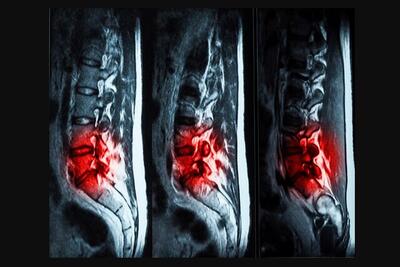

دیسک کمر با کمک فناورینانو قابل درمان میشود

دوینا پورمزور والتر استادیار مهندسی زیستپزشکی در دانشگاه ایالتی اوهایو گفت: « ما این راهبرد منحصر به فرد را ارائه کردیم